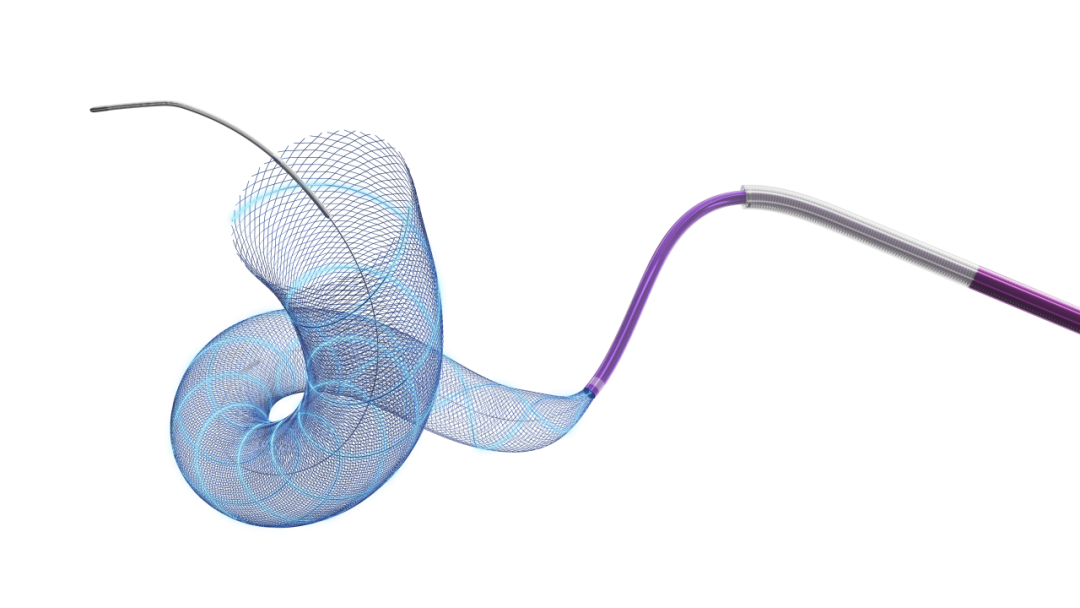

8F动脉短鞘、6F动脉长鞘+6F-115颅内支撑导管建立血管通路。工作位路图下输送Tubridge Plus(5.5*25)到达Fastrack27微导管远端,缓慢释放Tubridge Plus,头端由“V”形呈“U”形锚定贴壁。弯段释放过程中,继续保持Fastrack张力与Tubridge Plus支架张力的动态平衡状态,使Tubridge Plus每个节段与血管壁贴合。造影观察支架释放情况,支架在弯段打开良好,与血管壁贴合充分。

支架尾端释放,距离Tubridge Plus释放Mark5mm处,回撤微导管,完全释放张力,支架自然打开贴壁。撤出输送系统。

支架完全打开后,使用J型导丝按摩,促使Tubridge Plus每个节段与血管壁良好贴合。

术后正侧位造影,Tubridge Plus支架显影呈“两维3D”形态,支架每个节段实现充分贴壁效果,载瘤动脉通畅,未发现不良征兆。

术后稀释造影,3D显示Tubridge Plus支架与血管壁完美贴合。

Tubridge Plus血流导向密网支架是微创脑科学的经典血流导向密网支架Tubridge的第二代,进行了诸多升级:两维3D、全程显影;全系列适配27微导管;推送阻力明显下降等等。

置入Tubridge Plus支架过程中可以明显感受到支架推送更顺滑,支架打开更顺畅,而全程显影的支架让我对其贴壁的观察更为直观,总体使用感受良好。